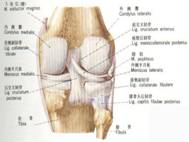

十字韌帶損傷膝關節內有前、後十字韌帶(又稱交叉韌帶),前十字韌帶起自脛骨髁間隆起的前方,向後、上、外止於股骨外髁的內面;後十字韌帶起自脛骨髁間隆起的後方、向前、上、內止於股骨內踝的外面,膝關節不論伸直或屈曲,前後十字韌帶均呈緊張狀態,前十字韌帶可防止脛骨向前移動,後十字韌帶可防止脛骨向後移動。

十字韌帶損傷ACL自脛骨髁間前區斜向外後上方,呈散開狀止於股骨外側髁的內側面後部,由前內側束、後外側束組成,前內側束較大而牢固,後外側束較小,ACL的功能是防止脛骨前移,並與側副韌帶、關節囊後部增厚部分一起限制膝關節過伸。ACL在MRI矢狀位顯示最清楚,T1WI、T2WI均表現為斜行的帶狀低信號,界限清楚,前緣均光滑,大部分後緣欠光滑。ACL在脛骨附著處的上方存在著脂肪和結締組織,信號強度較高。韌帶在此處分支,MRI常見分支間為高信號,應避免誤診為韌帶內信號異常。